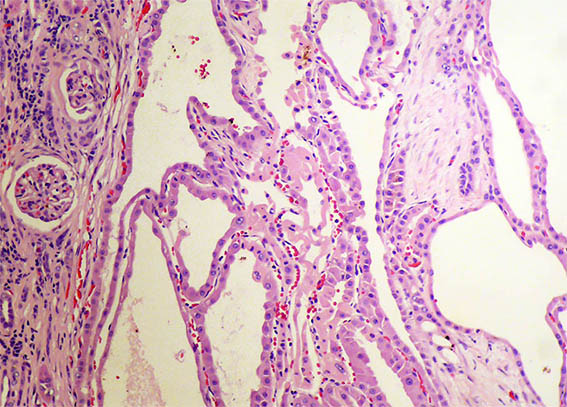

Figure 3. H&E, X100.